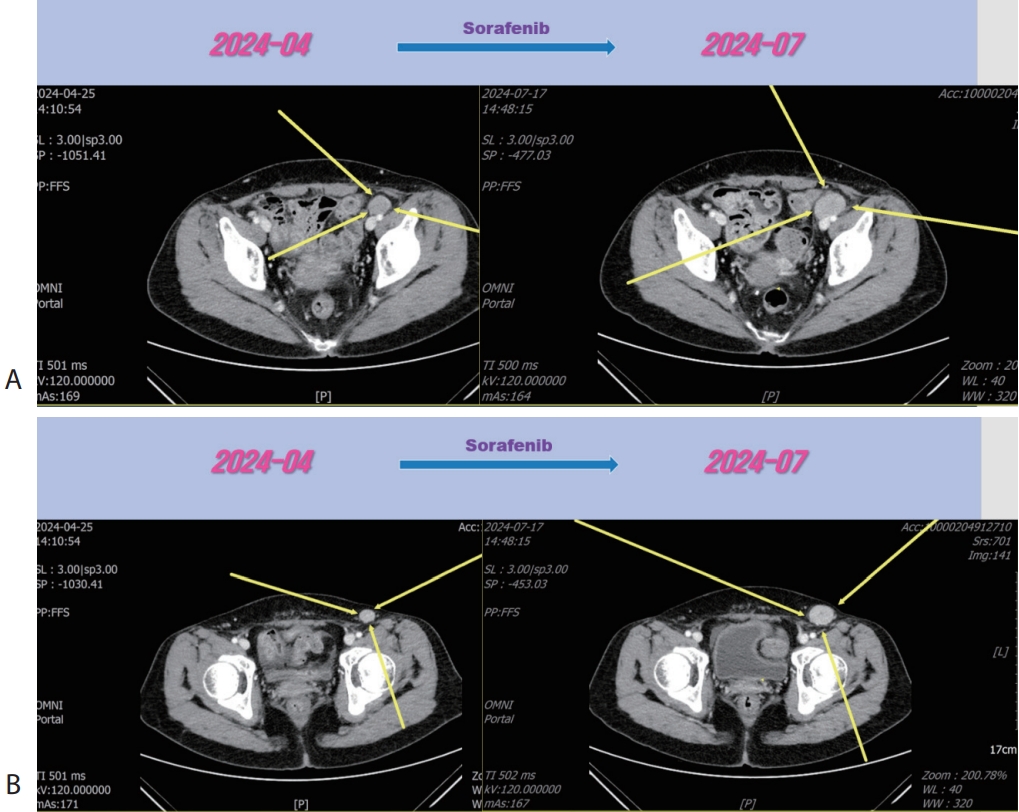

Fig. 4). Then the patient was treated with 2nd line sorafenib (Nexavar

®, 200 mg per dose; Bayer, Leverkusen, Germany) for 2 months, but LN metastasis was progressed (

Fig. 4). Then the patient was treated with 3rd line regorafenib (Stivarga

®, 40 mg per dose; Bayer) for 3 months and LN metastasis was slightly increased (

Fig. 5), then we decided to combine RT for LN metastasis (40 Gray/16 fraction). Then the LN metastasis was markedly decreased (

Figure 4.Liver CT scan (A, B) after 2nd line sorafenib therapy. New developed pelvic (A) and inguinal (B) lymph node metastasis were progressed after sorafenib therapy. CT, computed tomography.